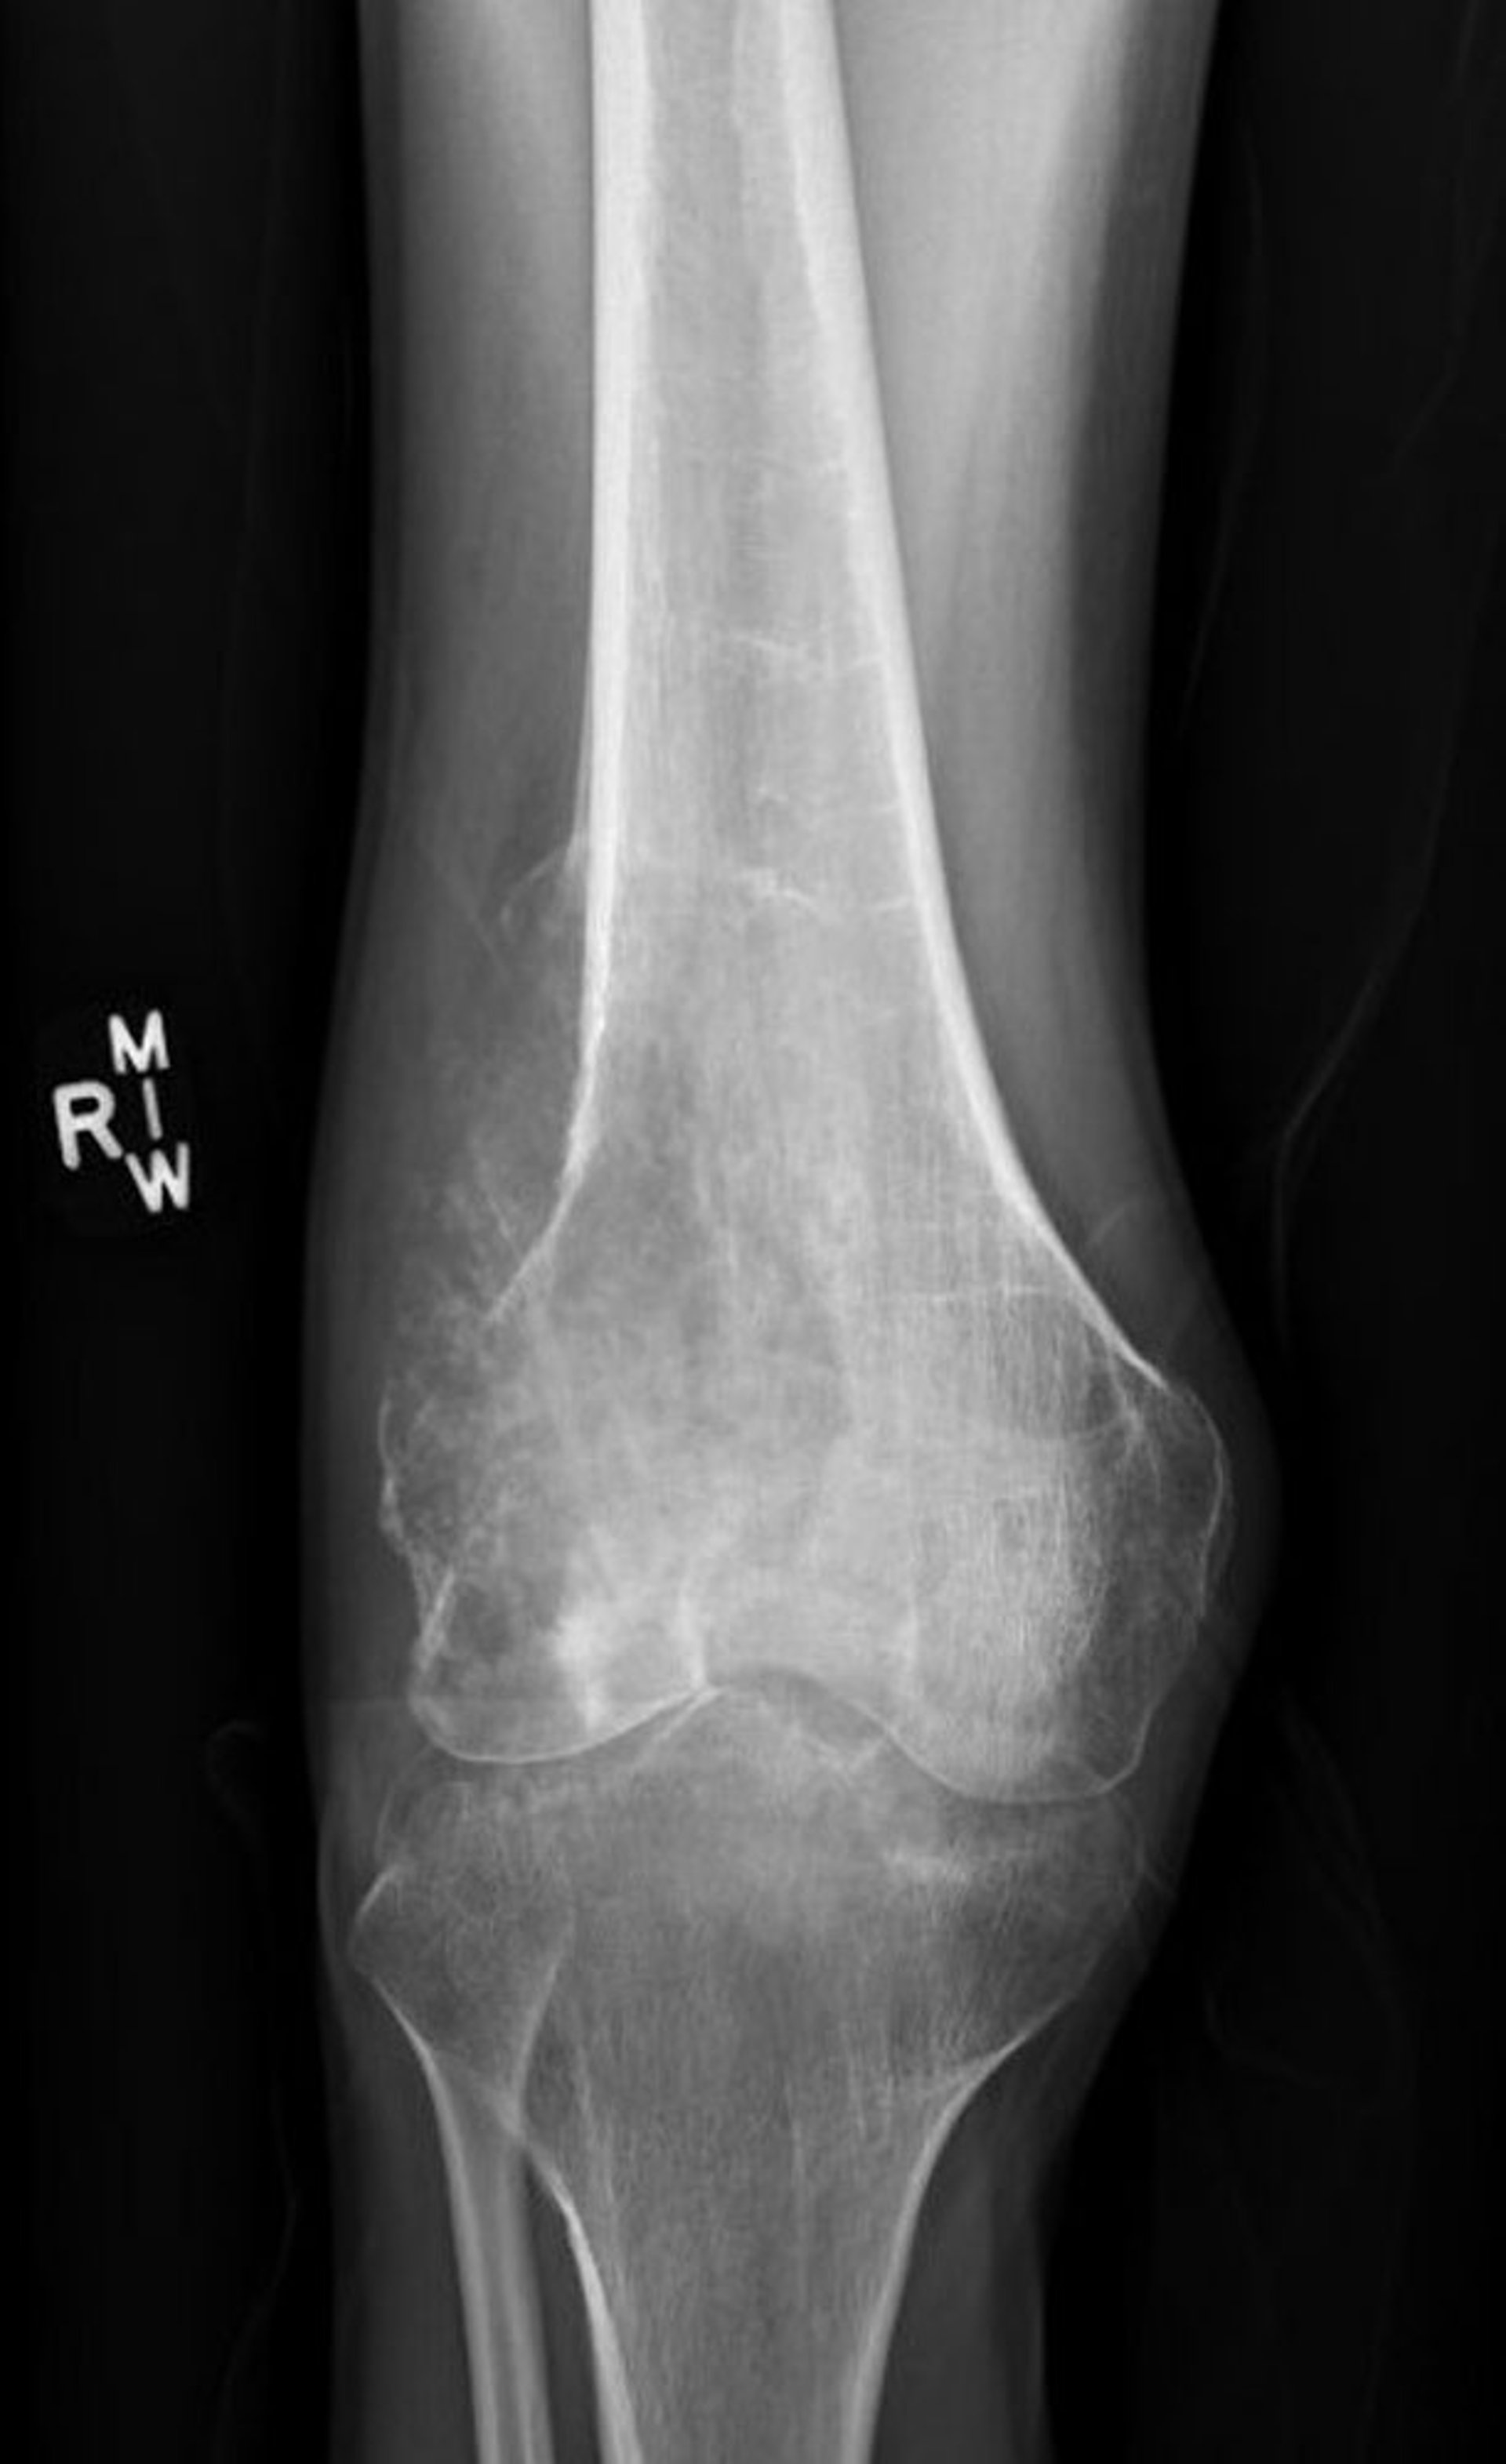

Phim chụp X-quang khớp gối này cho thấy một sarcoma xương cóphá hủy ở xương đùi phía trên khớp gối với biểu hiện phá hủy xương dạng tiêu xương và hình tam giác Codman cổ điển cho thấy dày màng xương bệnh lý.

Hình ảnh do bác sĩ Lukas Nystrom cung cấp.